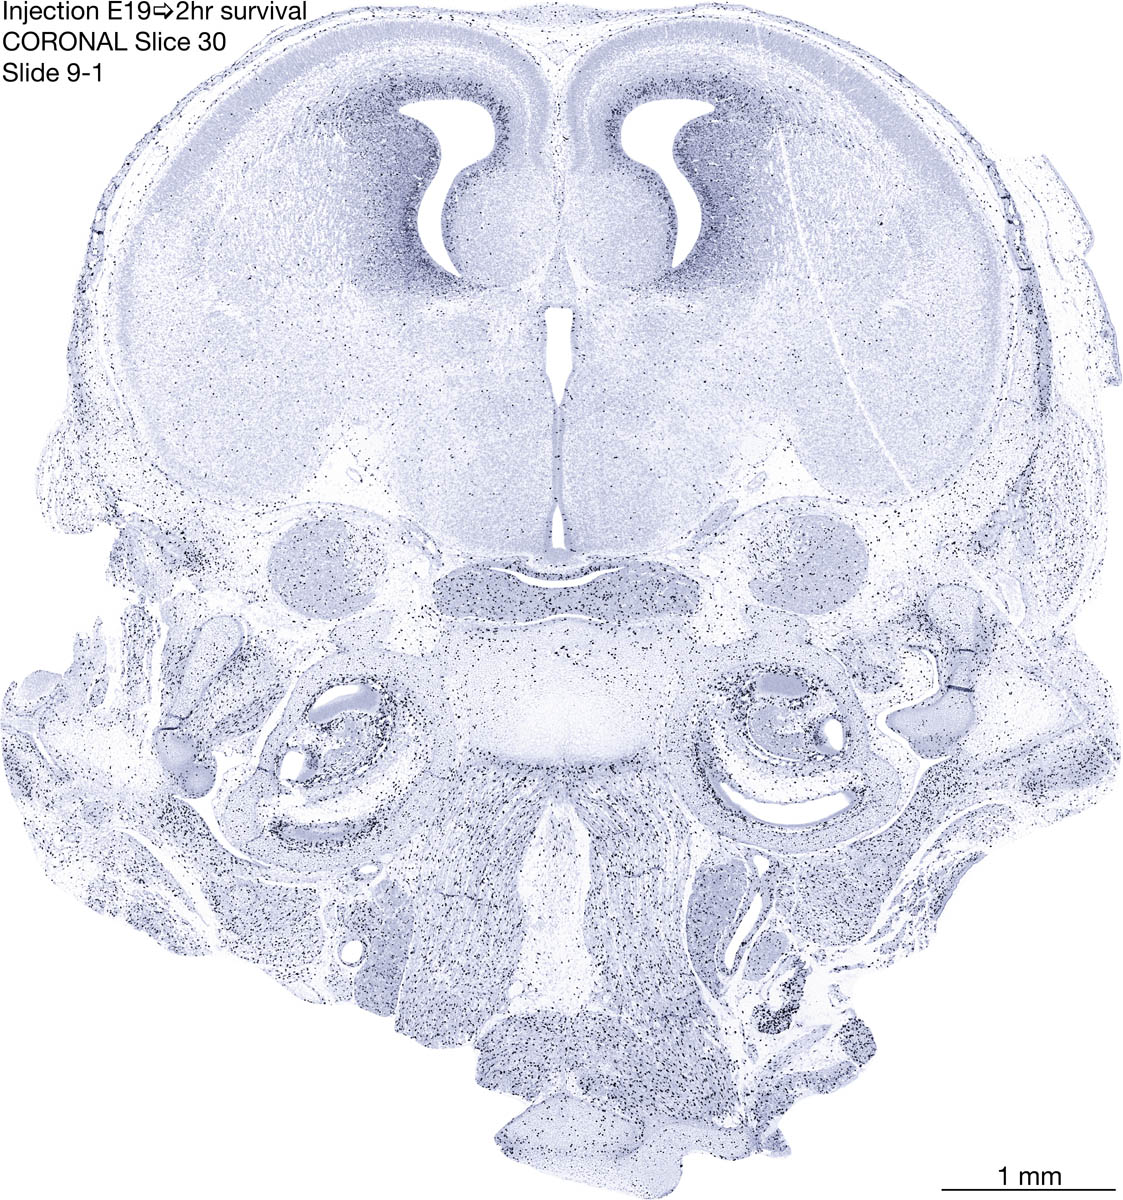

E19 2hr Survival Archived Images-Coronal The following images are from a paraffin-embedded coronally-sectioned head of an E19 rat embryo exposed to tritiated thymidine 2 hours before death. Download: Large | High Res Download: Large | High Res Download: Large | High Res Download: Large | High Res Download: Large | High Res Download: Large | High Res Download: Large | High Res Download: Large | High Res Download: Large | High Res Download: Large | High Res Download: Large | High Res Download: Large | High Res Download: Large | High Res Download: Large | High Res Download: Large | High Res Download: Large | High Res Download: Large | High Res Download: Large | High Res Download: Large | High Res Download: Large | High Res Download: Large | High Res Download: Large | High Res Download: Large | High Res Download: Large | High Res Download: Large | High Res Download: Large | High Res Download: Large | High Res Download: Large | High Res Download: Large | High Res Download: Large | High Res Download: Large | High Res Download: Large | High Res Download: Large | High Res Download: Large | High Res Download: Large | High Res Download: Large | High Res Download: Large | High Res Download: Large | High Res Download: Large | High Res Download: Large | High Res Download: Large | High Res Download: Large | High Res Download: Large | High Res Download: Large | High Res Download: Large | High Res Download: Large | High Res Download: Large | High Res Download: Large | High Res Download: Large | High Res Download: Large | High Res Download: Large | High Res Download: Large | High Res Download: Large | High Res Download: Large | High Res Download: Large | High Res Download: Large | High Res Download: Large | High Res Download: Large | High Res Download: Large | High Res Download: Large | High Res Download: Large | High Res Download: Large | High Res Download: Large | High Res Download: Large | High Res Download: Large | High Res Download: Large | High Res Download: Large | High Res Download: Large | High Res Download: Large | High Res Download: Large | High Res Download: Large | High Res Download: Large | High Res Download: Large | High Res Download: Large | High Res Download: Large | High Res Download: Large | High Res Download: Large | High Res Download: Large | High Res Download: Large | High Res Download: Large | High Res Download: Large | High Res Download: Large | High Res Download: Large | High Res Download: Large | High Res Download: Large | High Res Download: Large | High Res Download: Large | High Res Download: Large | High Res Download: Large | High Res Download: Large | High Res